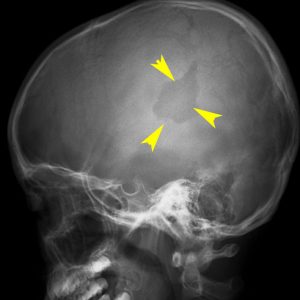

- レントゲン検査で,頭蓋骨が丸くポコンと抜けるように溶けているのが特長です

頭蓋骨のLCH

- 上の写真は,子供の右の頭頂骨にできたLCHで,頭部病変では最も多く見られるタイプです

- 頭蓋骨が丸く抜けるように破壊されるのでpunched out lesionと表現されます